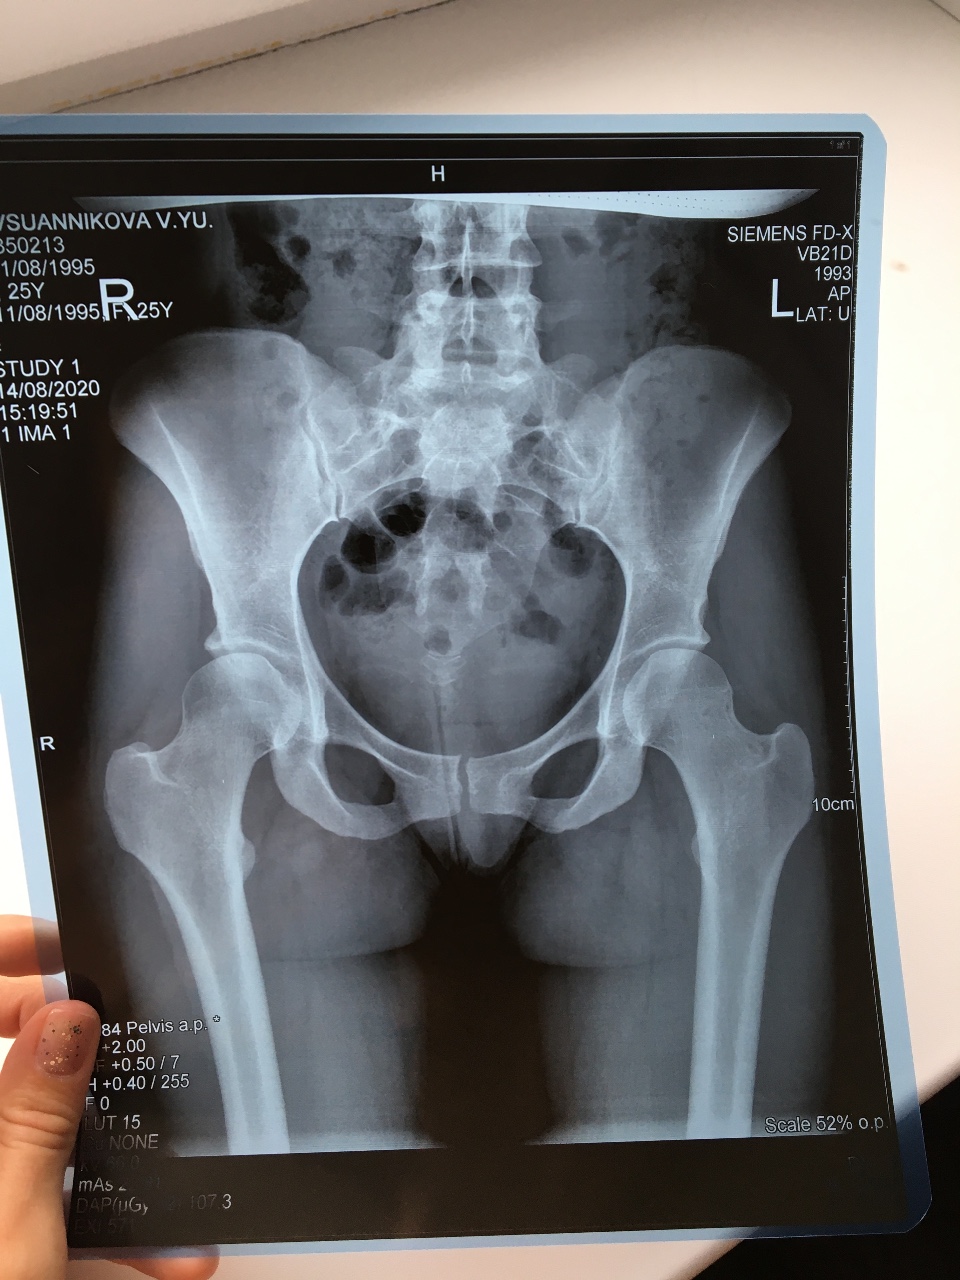

Рентгеновские снимки плат в высоком разрешении

Раздел: Точки зрения